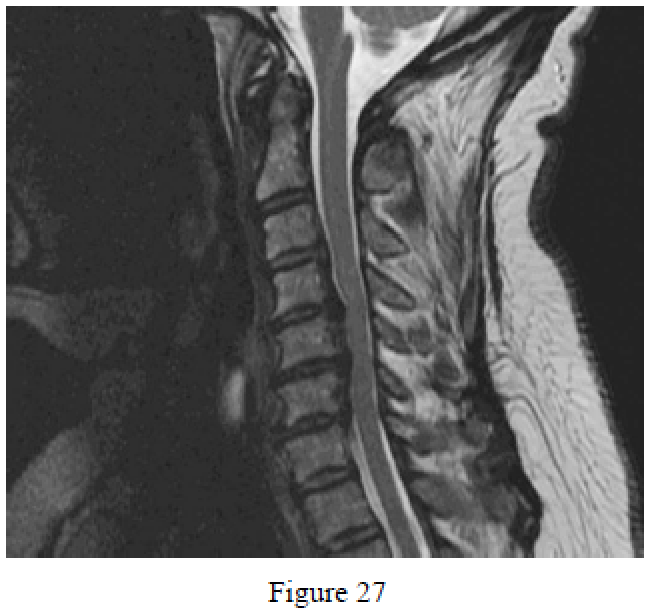

Question 27

Figure 27 is the MR image of a 68-year-old woman who has had neck pain for several years. She has noticed progression of gait imbalance and changes in her handwriting. What is the best next step?